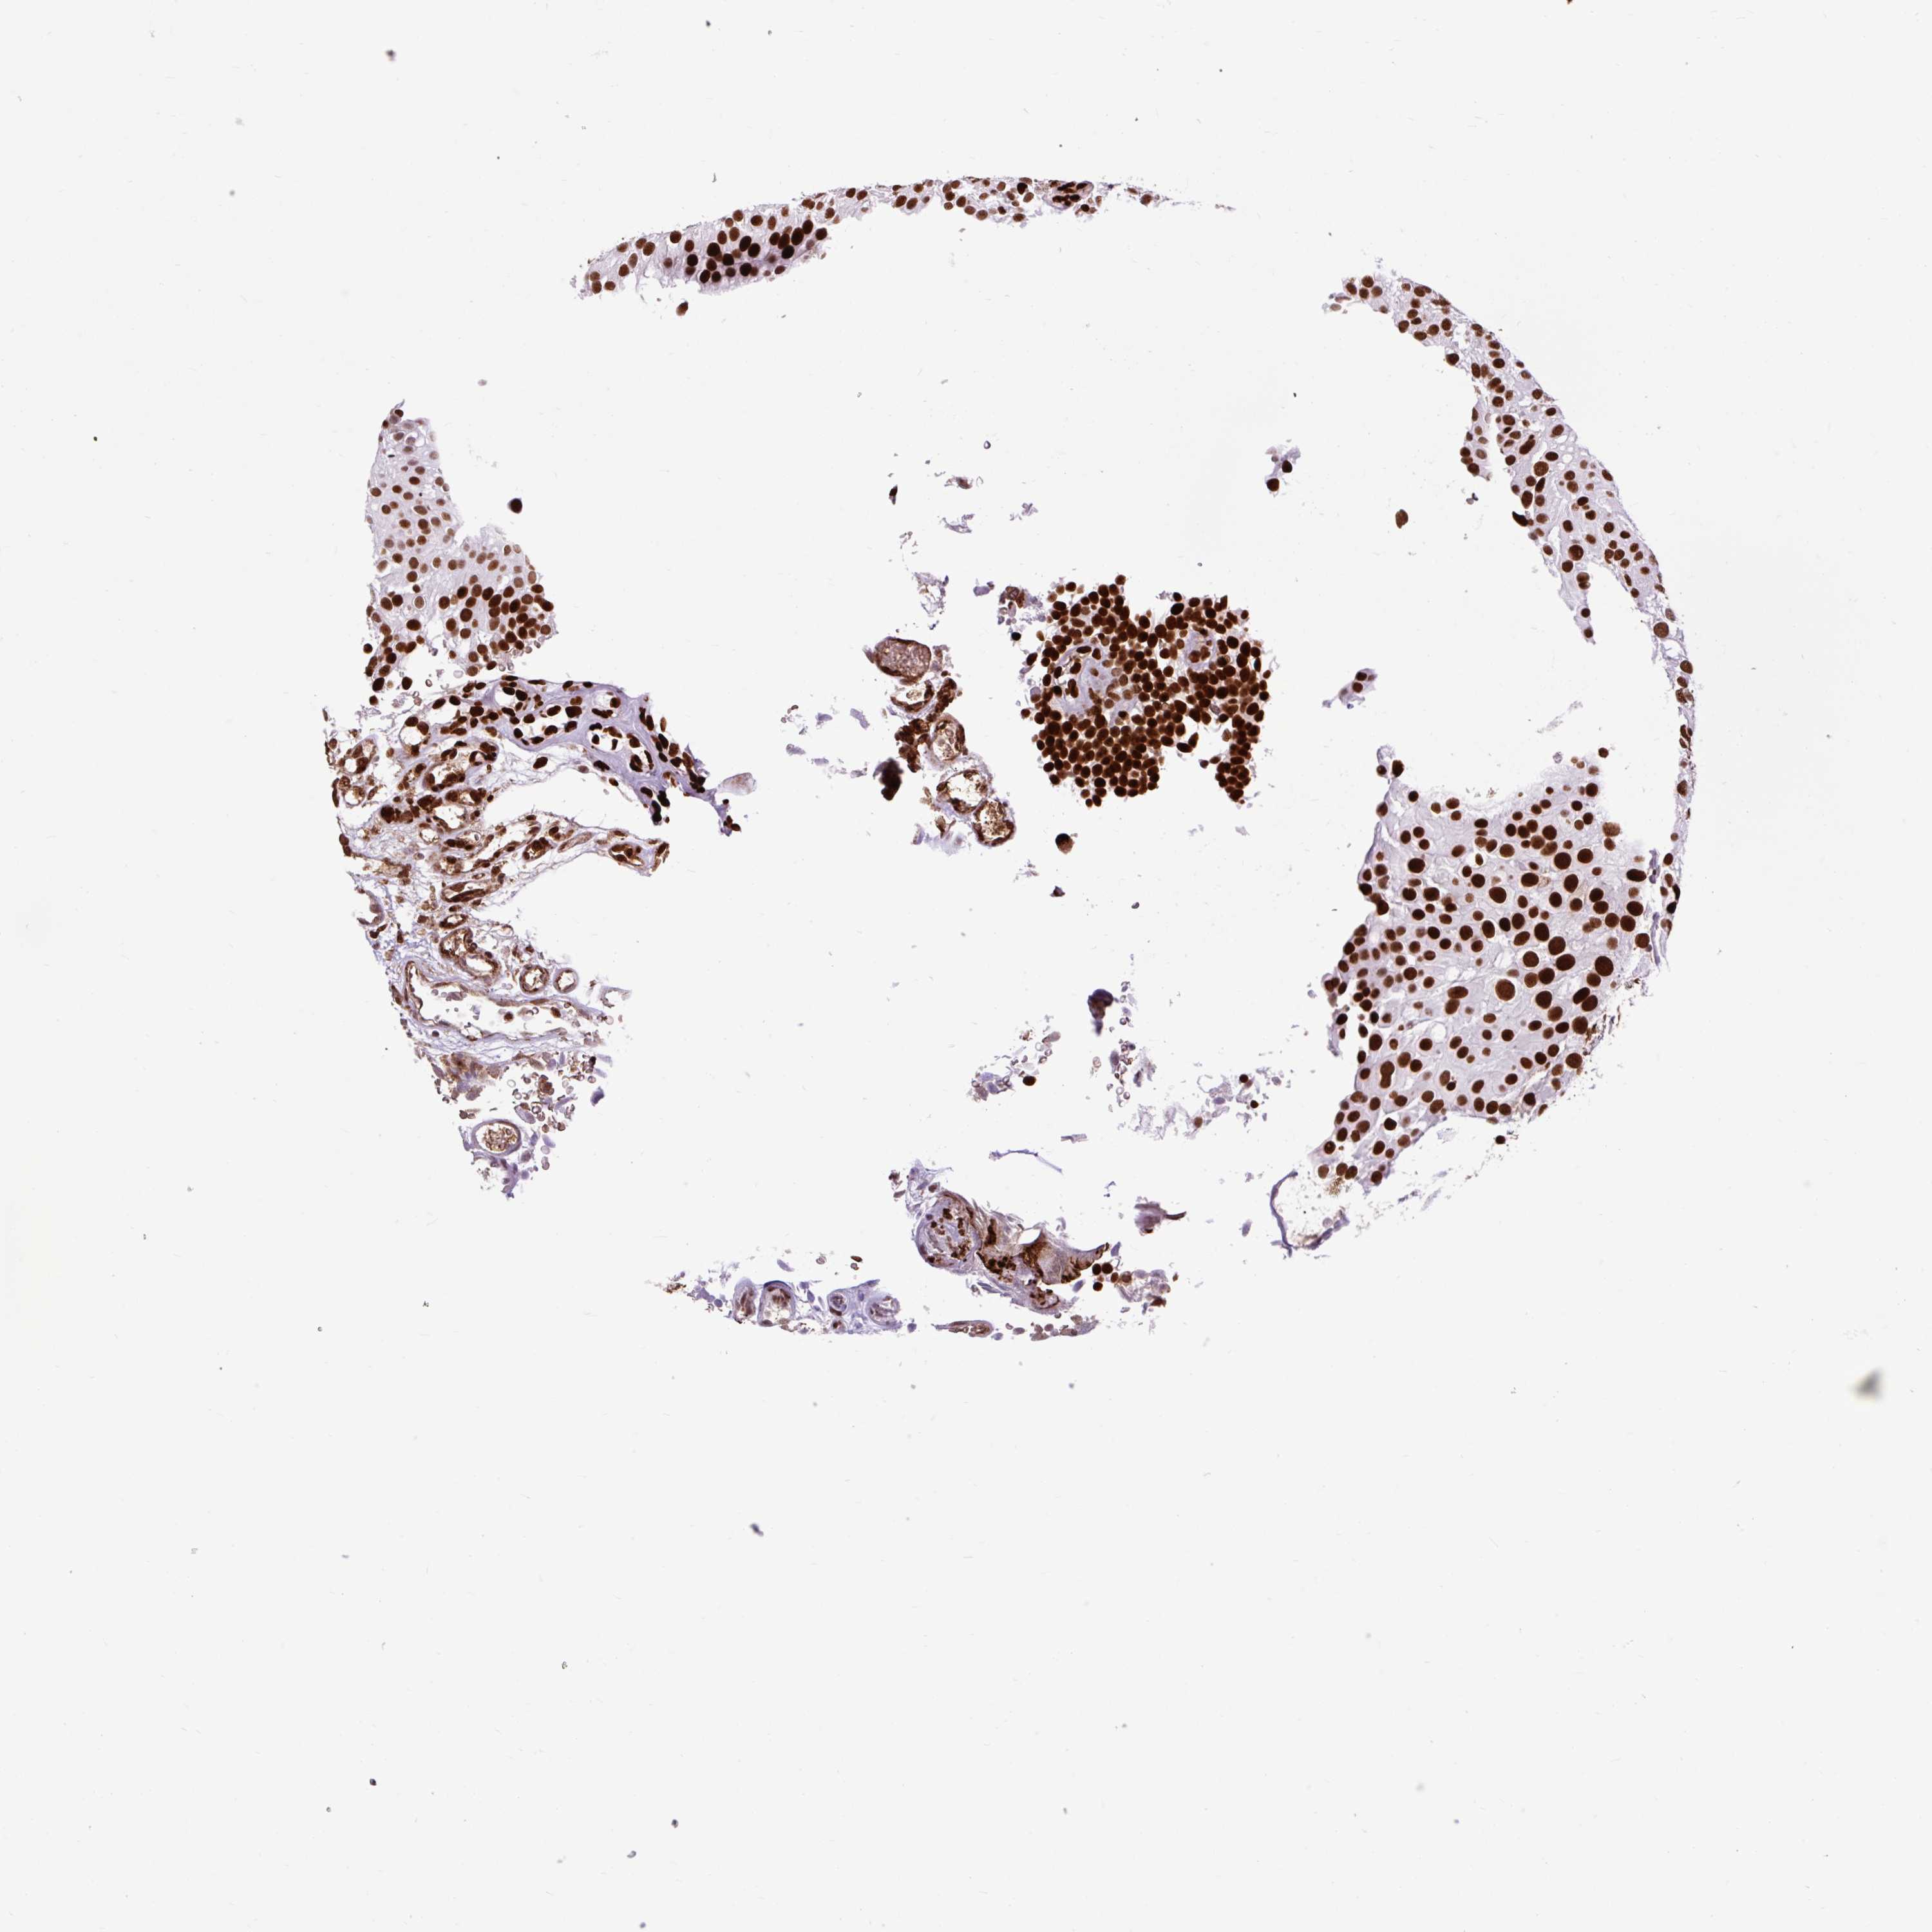

UROTHELIAL CANCER - Protein expressioni

A mouse-over function shows sample information and annotation data. Click on an image to view it in a full screen mode. Samples can be filtered based on level of antibody staining by selecting one or several of the following categories: high, medium, low and not detected. The assay and annotation is described here.

Note that samples used for immunohistochemistry by the Human Protein Atlas do not correspond to samples in the TCGA dataset.

Antibody stainingi

Antibody staining in the annotated cell types in the current human tissue is reported as not detected, low, medium, or high, based on conventional immunohistochemistry profiling in selected tissues. This score is based on the combination of the staining intensity and fraction of stained cells.

Each image is clickable and will lead to virtual microscopy that enables deeper exploration of all samples and also displays staining intensity scores, fraction scores and subcellular localization as well as patient and tissue information for each sample.

Antibody HPA008784

Antibody CAB033036

Antibody CAB058691

Staining

High

Medium

Low

Not detected

Intensity

Strong

Moderate

Weak

Negative

Quantity

>75%

75%-25%

<25%

None

Location

Nuclear

Cytoplasmic/membranous

Cytoplasmic/membranous,nuclear

Urothelial carcinoma, Low grade

Urothelial carcinoma, High grade

Urothelial carcinoma, NOS